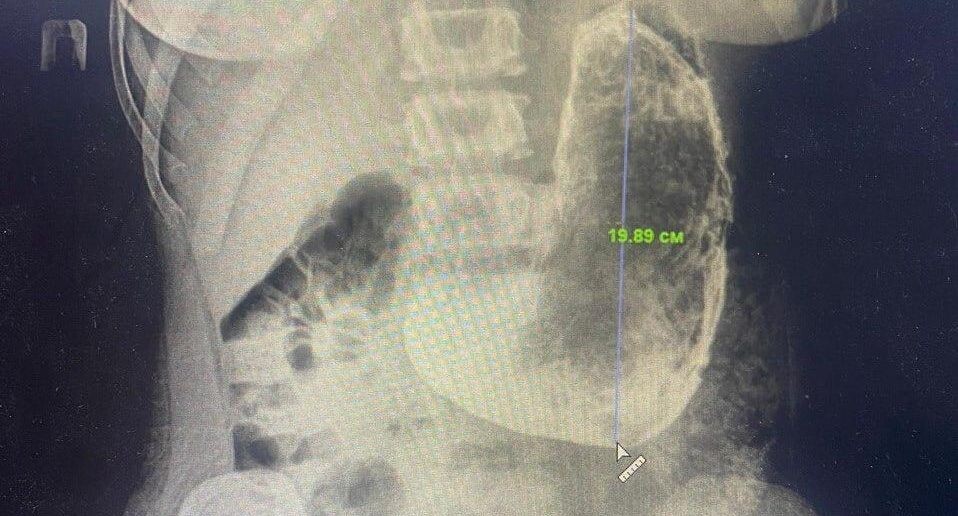

Врачи Красногорской больницы спасли 19-летнюю девушку с крупным новообразованием в желудке. Пациентка поступила в медицинское учреждение с жалобами на рвоту и сильные боли в животе. Специалисты провели обследование и обнаружили в просвете желудка инородное тело, размер которого составлял 20 на 15 сантиметров. Девушка призналась, что последние пару месяцев принимала препараты для снижения веса, купленные онлайн. «Из-за больших размеров и плотной консистенции желудочного камня, мы приняли решение провести операцию, в ходе которой удалили образование через небольшой разрез», — пояснил заведующий хирургическим отделением Красногорской больницы Николай Мурашов. Сейчас пациентка готовится к выписке. Врачи призвали не принимать никакие препараты без назначения специалиста. Автор: Елизавета Теличенко

Специалисты провели обследование и обнаружили в просвете желудка инородное тело, размер которого составлял 20 на 15 сантиметров. Девушка призналась, что последние пару месяцев принимала препараты для снижения веса, купленные онлайн.

«Из-за больших размеров и плотной консистенции желудочного камня, мы приняли решение провести операцию, в ходе которой удалили образование через небольшой разрез», — пояснил заведующий хирургическим отделением Красногорской больницы Николай Мурашов.